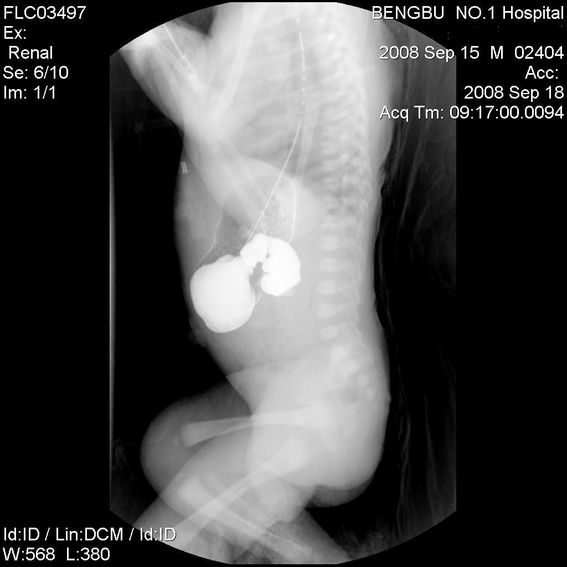

十二指肠降部钡流不能顺利通过,胃及十二指肠球扩张。

考虑----十二指肠降部狭窄-----〔但这几个片子狭窄未能清楚显示,无法判断分型-----膜性或管状〕

考虑----十二指肠降部狭窄

十二指肠降部狭窄(可能为环状胰腺)。

十二指肠降部钡流不能顺利通过,胃及十二指肠球扩张,符合十二指肠降部狭窄